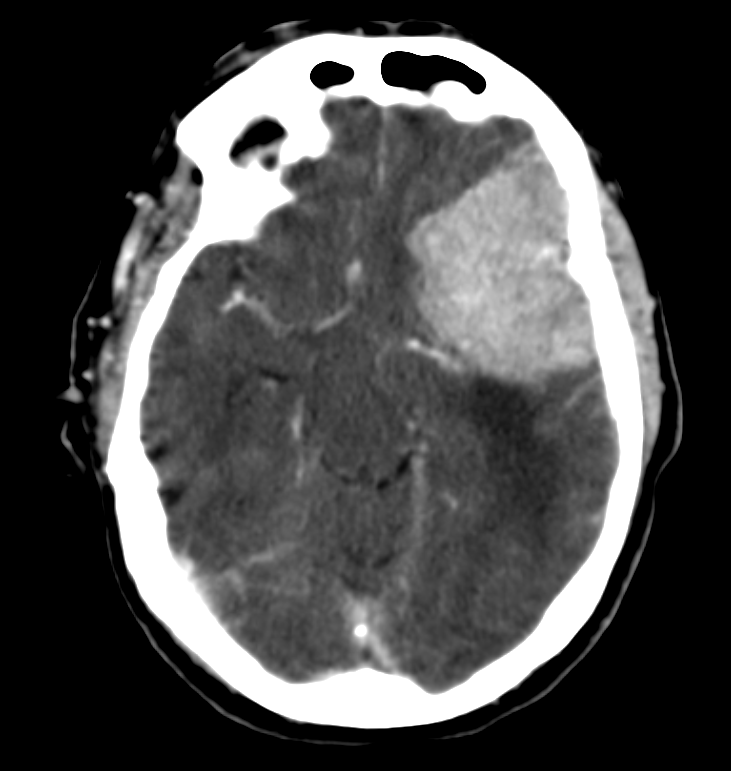

Transtentorial: puede ser unilateral/uncal o bilateral/central.

- Puede ser unilateral o Uncal = descenso del uncus hacia el interior de la cisterna supraselar.

- Dilatación del asta lateral contraletaral

- Dilatación de la cisterna ambiens y prepontina ipsilateral.

- Bilateral o Central = obliteración las cisternas basales

- Hay riesgo de infartos por compresión la ACP y perforantes.

- Pueden producir hemorragias de Duret (mesencéfalo) o de Kreonhan (pedúnculo cerebral contralateral)